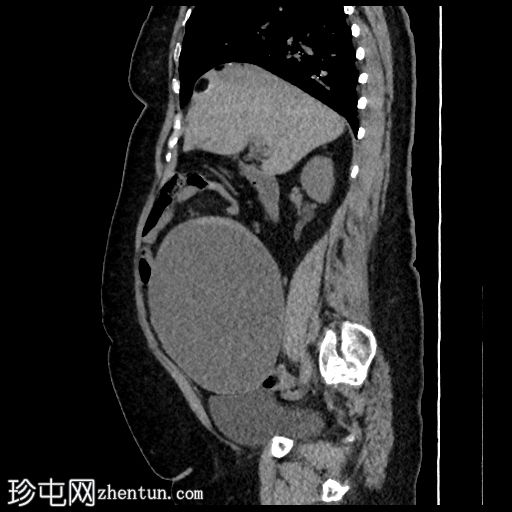

矢状位

平扫

肝脏VIII段可见边界清晰的含液和脂肪的病变,边缘可见钙化,符合卵巢畸胎瘤肝包膜沉积。

腹盆腔可见较大的规则、薄壁病变,主要为液体,内部可见含脂肪的小叶和边缘钙化,符合卵巢畸胎瘤的影像学表现。